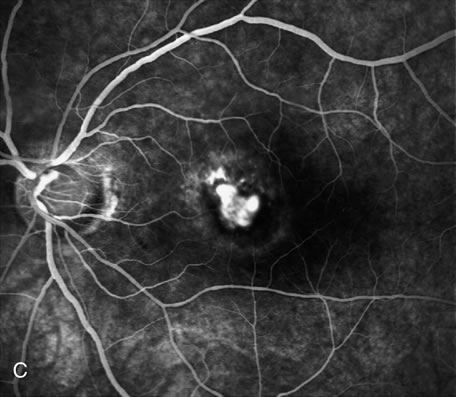

Fig. 16. Subfoveal, juxtafoveal, and extrafoveal choroidal neovascular membranes. A and B. Large subfoveal choroidal neovascularization (CNV) in a 69-year-old man with blood and pigment blocking central fluorescence on both the early-phase (A) and late-phase (B) photographs. The hypofluorescence surrounding the membrane is commonly seen in CNV and may be due to lipofuscin. C. Juxtafoveal CNV in a 37-year-old man with idiopathic CNVM. D. Cuticular drusen in same patient as in C were asymptomatic. E. Years later, this same patient developed a large extrafoveal CNV with central macular pigment abnormalities. A large neurosensory detachment was responsible for the disappearance of the drusen. (Courtesy of Dr. Kenneth G. Noble.)

Conventional laser thermophotocoagulation is the treatment of choice for extrafoveal, well-defined, classic CNV. Photodynamic treatment (PDT) is the treatment of choice for subfoveal, predominantly classic CNV. FA is used to localize the lesion in relation to the fovea, classify the subtype, choose the type of procedure, and guide the treatment (Figs. 18, 19, and 20).56–73